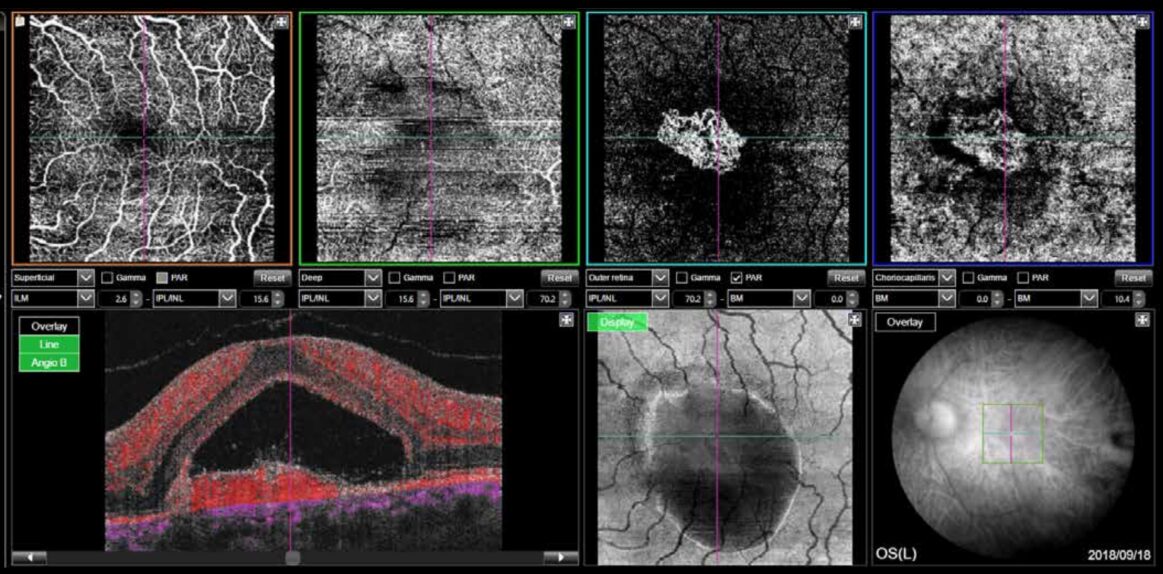

OCT Angiografie

Met één druk op de knop biedt de Maestro2 een densitometrie-map zonder dat er contrastvloeistof hoeft te worden geïnjecteerd, samen met uitgebreide segmentatie voor geavanceerde diagnose.

Choroïdale neovascularisatie (CNV)